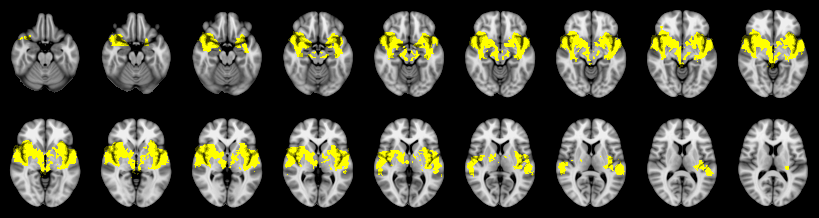

Pain study, Cluster extent, Corrected

Not combined

Combined

Stouffer: